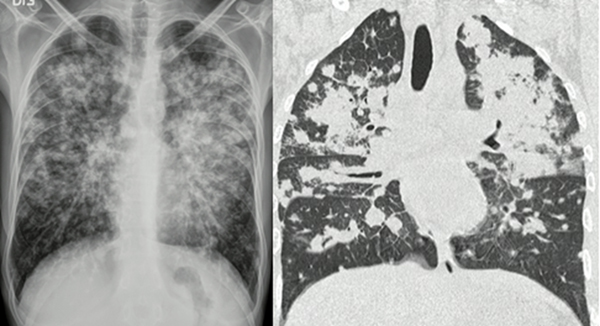

El sarcoma de Kaposi es una neoplasia de origen endotelial asociada a la infección por virus herpes humano tipo 8. En la actualidad, es más frecuente encontrarlo en individuos con recuentos de CD4+ muy disminuidos, y uno de los factores que predisponen a exacerbación de las lesiones es el síndrome inflamatorio de reconstitución inmune (48,49). Cursa con síntomas inespecíficos dados por tos, disnea y fiebre, y con menor frecuencia hay hallazgo de lesiones mucocutáneas. En estudios de imágenes se puede observar engrosamiento de las paredes bronquiales y un patrón nodular con morfología en llama (figura 3). Durante la fibrobroncoscopia es posible encontrar lesiones endobronquiales maculares purpúricas o eritematosas, especialmente en las bifurcaciones de la vía aérea. Su tratamiento incluye el uso de terapia antirretroviral, con buena repuesta en la mayoría de los casos (48,50).